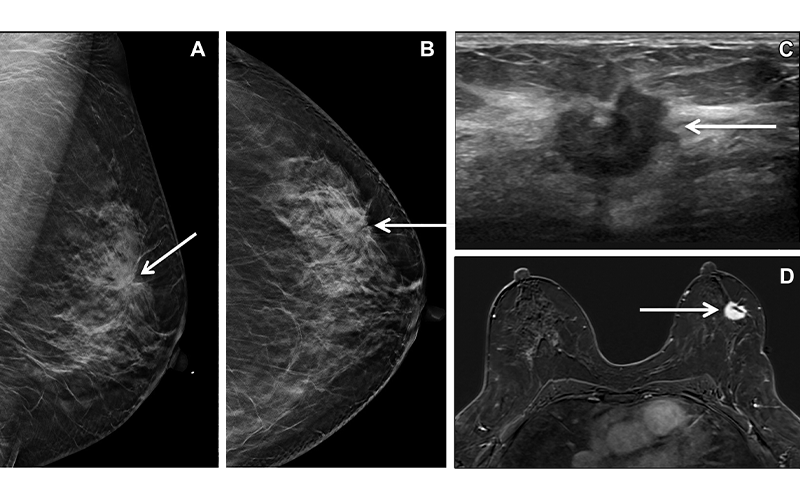

Breast cancer screening in a 53-year-old Asian American woman of Indian descent who was a recent immigrant and medical translator. (A, B) Left breast mediolateral oblique (A) and craniocaudal (B) in-plane tomographic mammograms show a spiculated mass (arrow). (C) US image shows a corresponding 1.8-cm irregular mass (arrow) at the 2-o’clock position, 4 cm from the nipple, that was sampled at biopsy and found to be ER- and PR-positive, HER2-negative IDC. (D) Staging MR image shows the same mass (arrow) in the left breast. https://doi.org/10.1148/rg.220074 ©RSNA 2022